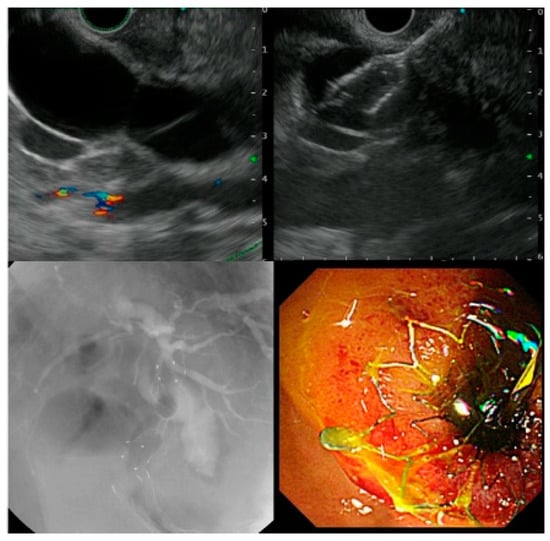

For the EUS-CDS procedure, the extrahepatic bile duct was visualized from the duodenal bulb using a linear endoscopic ultrasound (GF-UCT260; Olympus Medical Japan, Tokyo, Japan). The extrahepatic bile duct was punctured using a 19-G puncture needle, and a guidewire was placed in the bile duct. The fistula was then dilated using a dilation device, and a plastic stent (PS) or a self-expandable metal stent (SEMS) was deployed (Figure 1).

Figure 1.

Procedure of endoscopic ultrasound-guided choledochoduodenostomy.